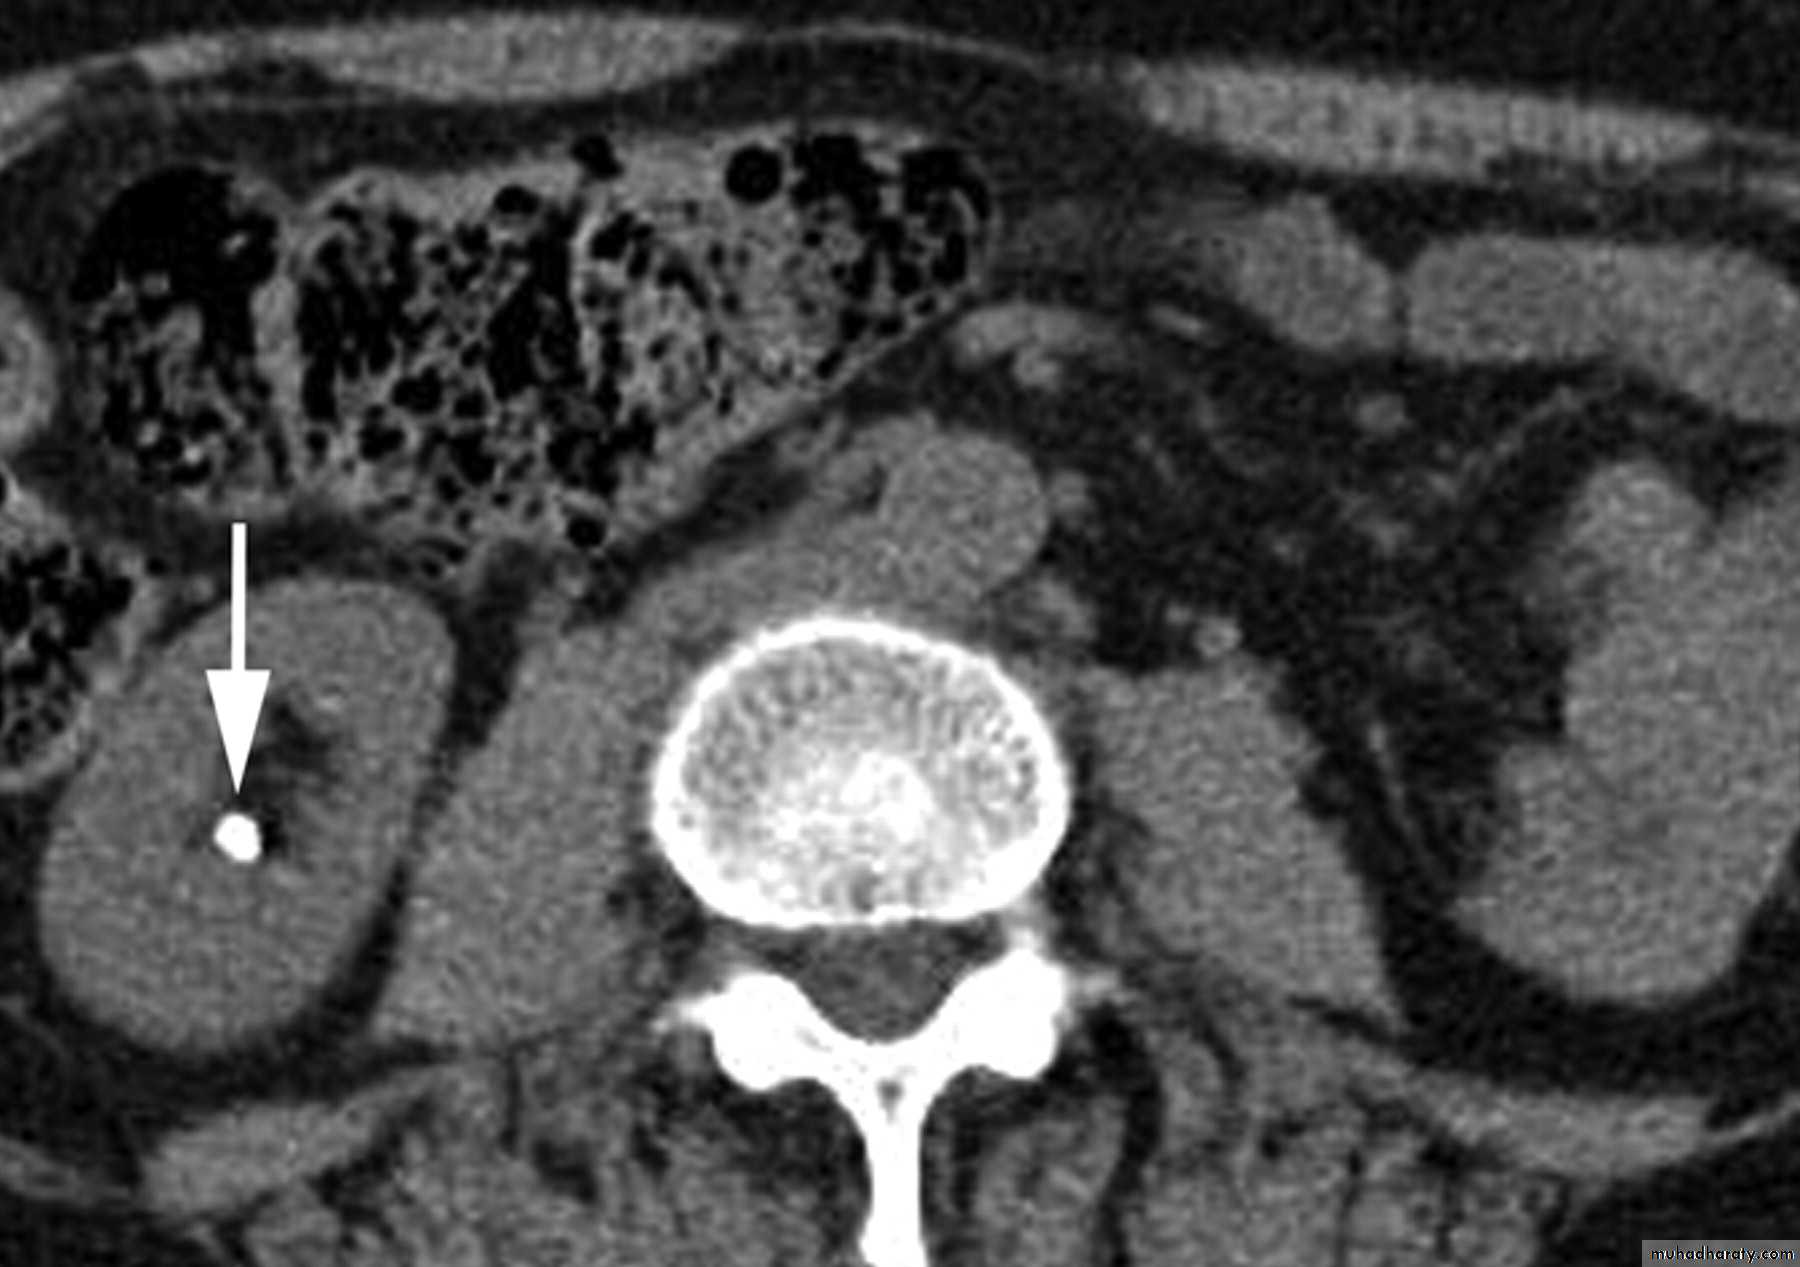

CT scans used in some hospitals during acute renal stone-Non contrast CT sensitively identify calculi and non opacified collecting system down to the level of obstruction. it has a sensitivity of 97% and specificity of 96% for detection of ureteral calculi